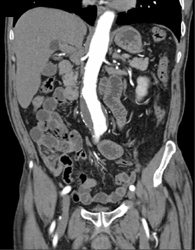

Collaterals Due to Cavernous Transformation of the Portal Vein (CTPV) Well Defined